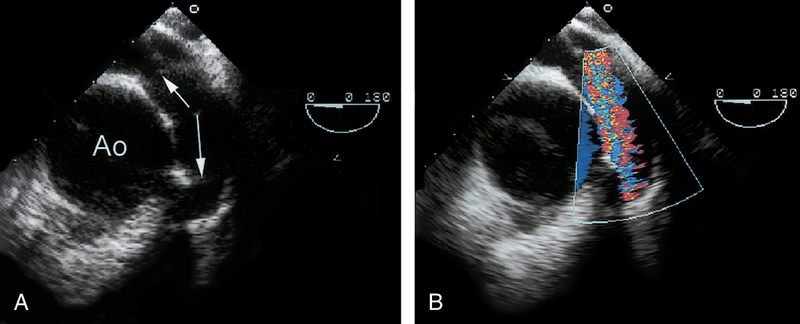

فحوصات تشخيصية لبعض امراض القلب والشرايين التاجية